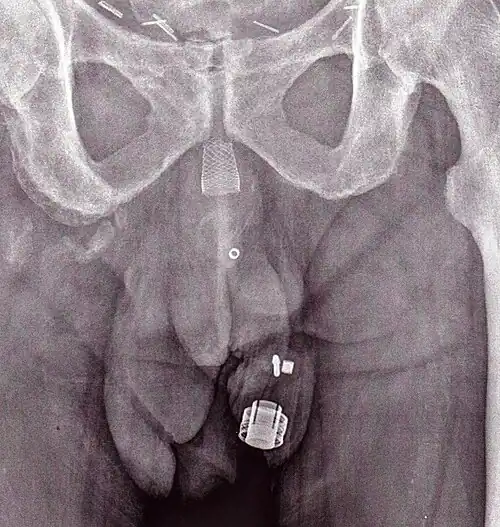

Radiographie d'un ZSI 375 implanté. Le dispositif est désactivé: le ressort est sous le sommet du cylindre. Le patient est incontinent.

Radiographie d'un ZSI 375 implanté. Le dispositif est activé: le ressort est au niveau du sommet du cylindre. Le patient est continent.